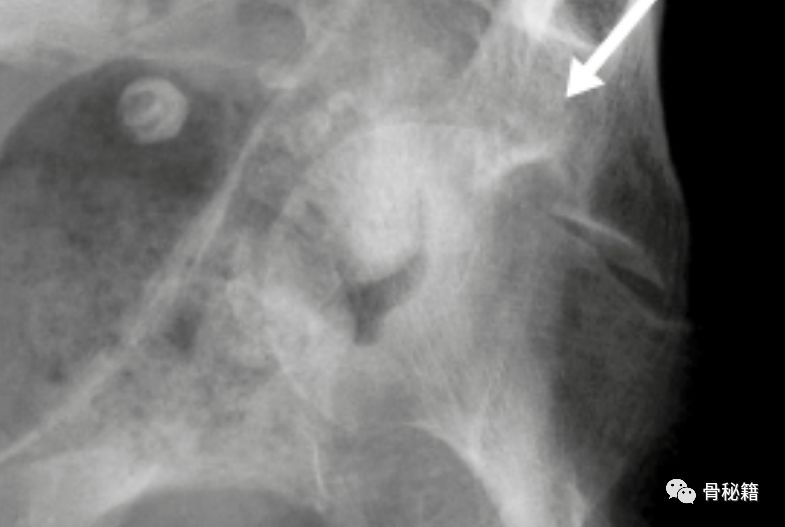

术前的CT和X线都是很好的工具,通过影像学来分辨臼顶到底有没有压缩,压缩了多少。

红色为压缩后,绿色为压缩前。

这种臼顶的压缩还有个特殊的名字叫海欧征,髋臼匹配度出现了问题,这个时候就需要注意有臼顶压缩了。

CT图像可以更好的分辨是否压缩还有压缩的数值,还有具体的方位,是前方 还是后方?内侧还是外侧?